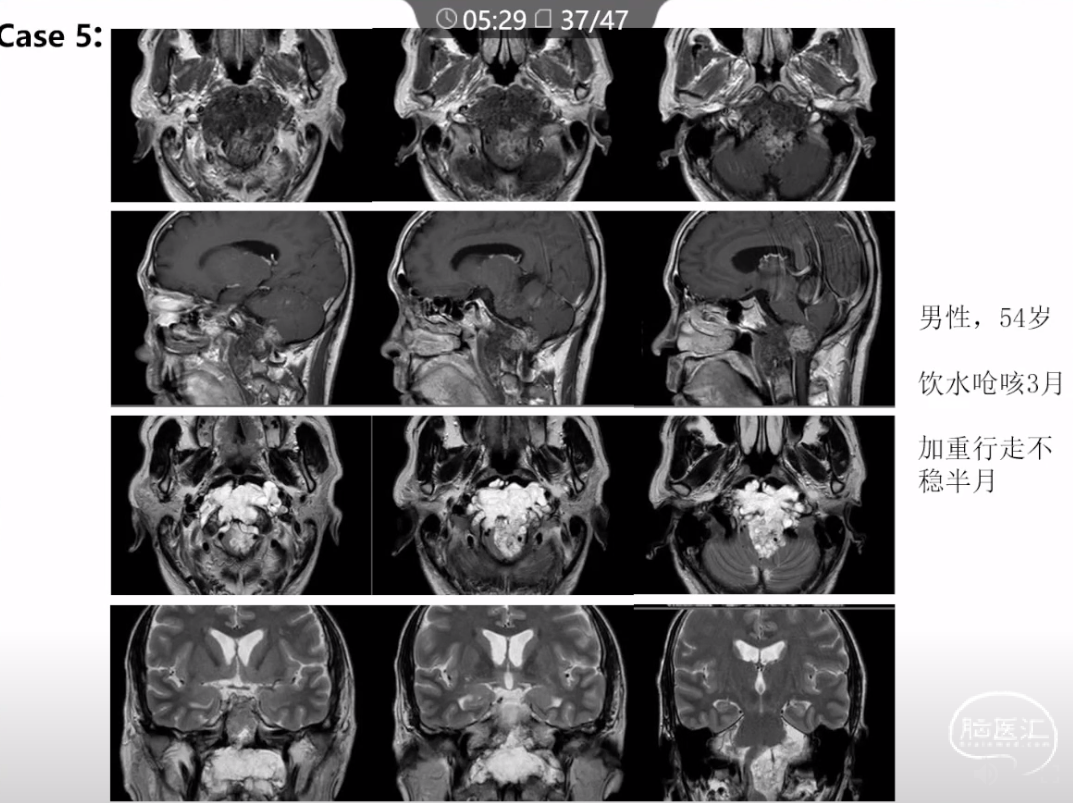

本文主要内容为:脊索瘤临床特点、治疗选择,以及多个手术病例。